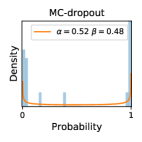

5.1 Distribution of Uncertainty Scores

Distribution of Uncertainty Scores Across Different Severity Levels As explained in Section 3, each uncertainty metric essentially defines an order/ranking among the data points. We conducted an analysis to better understand what data will be assigned high uncertainty under a particular uncertainty metric . Picking out the highest ranked data points (), we calculated the ratio of data points from each SL. Figure 4 summarizes the results as box plots for the Kaggle-DR and the Messidor-2 datasets; additional detailed statistics can be found in Table S.1 in the supplementary materials. From the plot and table, SL1 & SL2 examples account for a higher proportion among the top-ranked uncertain examples across the three ensemble methods. This finding matches our intuition that incipient disease examples (SL1 & SL2) are more likely to be considered uncertain by ensemble methods due to their ambiguity.

Comparing the three ensemble methods in Figure 4, the stacking ensemble method has the highest ratios of SL1 & SL2 data among the high-uncertainty examples it identified under both mean and var. TTA showed slightly better performance than MC-dropout but still falls behind the stacking ensemble method. Considering the fact that SL0 examples accounted for the majority of the dataset, the stacking ensemble method was much more precise (specific) in selecting truly ambiguous data points that were difficult to classify. From Figure 3, we can also see that the stacking ensemble method greatly outperformed the other two methods in finding false negatives under both mean and var uncertainty metrics.

In contrast, the MC-dropout method showed the worst overall performance among the three, as it can be seen from the high ratios of SL0 examples among the uncertain negatives in Figure 4. The histograms in Figure 2 provides another perspective to look into the phenomenon, where a decent proportion of MC-dropout model’s predictions on SL0 inputs entailed low confidence (far from 0 or 1), which from another angle explained why MC-dropout was less specific in terms of lower FNP; many no-DR inputs (i.e. SL0) were erroneously assigned high uncertainty by MC-dropout models.

It is still an open question why the evaluated MC-dropout networks signaled relatively high uncertainty on SL0 & SL3 & SL4 data that are less likely to be ambiguous. We conjecture that much of the “uncertainty” indicated by disagreement among test-time dropout samples actually reflects the stochastic nature of dropout networks rather than the real decision uncertainty associated with the data. It is worth noting that the MC-dropout model we evaluated was not weak per se; they all achieved above Area Under Curve (AUC) scores on test sets. The weakness of individual test-time samples (which explains their low-confidence predictions on SL0 & SL3 & SL4) might have been hidden when they are aggregated into an ensemble—a well-known advantage of ensemble learning. Our results suggested that the uncertainty information given by implicit ensemble methods such as MC-dropout and TTA might not be as reliable as that from explicit ensemble approaches (e.g., stacking ensembles). Similar findings on MC-dropout can be found in some previous papers [1].